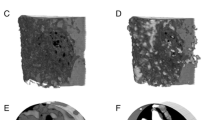

Bone formation in a variety of contexts depends on angiogenesis; however, there are few reports of the vascular response to osteogenic skeletal loading. We used the rat forelimb compression model to characterize vascular changes after fatigue loading. The right forelimbs of 72 adult rats were loaded cyclically in vivo to one of four displacement levels, to produce four discrete levels of ulnar damage. Rats were killed 3–14 days after loading, and their vasculature was perfused with silicone rubber. Transverse histological sections were cut along the ulnar diaphysis. We quantified vessel number, average vessel area, total vessel area, and bone area. On day 3, we observed a dramatic periosteal expansion near the ulnar midshaft, with significant increases in periosteal vascularity; total vessel area was increased 250–450% (P < 0.001). Vascularity remained elevated on days 7 and 14. Vessel number and average vessel area were not correlated (P = 0.09) and contributed independently to total vascular increases. Bone area was not increased on day 3 but on days 7 and 14 was increased significantly in all displacement groups (P < 0.01) due to periosteal woven bone formation. Vascular and bone changes depended on longitudinal location (P < 0.001), with peak increases 2 mm distal to the midshaft. Vascular and bone changes also depended on displacement level (P < 0.005), with greater increases at higher levels of fatigue displacement. We conclude that skeletal fatigue loading induces a rapid increase in periosteal vascularity, followed by an increase in bone area. The angiogenic-osteogenic response is spatially coordinated and scaled to the level of the mechanical stimulus.

Guldberg RE, Ballock RT, Boyan BD, Duvall CL, Lin AS, Nagaraja S, Oest M, Phillips J, Porter BD, Robertson G, Taylor WR (2003) Analyzing bone, blood vessels, and biomaterials with microcomputed tomography. IEEE Eng Med Biol Mag 22:77–83